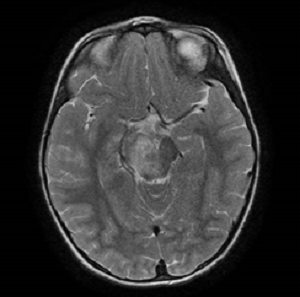

Se realiza resonancia magnética (RM) cerebral, que evidencia lesión mal definida de unos 3,1 × 3,6 cm, heterogénea, hiperintensa en T2 y flair con algunas calcificaciones puntiformes, centrada en pedúnculo cerebral derecho con carácter expansivo. Extensión caudal hacia protuberancia y paramedial izquierda hacia pedúnculo cerebeloso superior derecho. Se extiende también al tálamo derecho. alcanzando el brazo posterior de la cápsula interna, hipocampo y uncus derecho, con afectación corticosubcortical. Presenta mínimo edema perilesional, provocando engrosamiento parcial en la región derecha del quiasma óptico. Produce discreto efecto de masa con parcial obliteración ventricular.